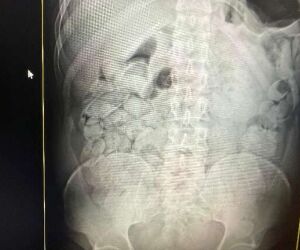

Na operação de quarta-feira, dos 18 presos, 17 haviam engolido cápsulas de droga. Cada um ingeriu aproximadamente 100 cápsulas, totalizando cerca de 1,1 quilo por pessoa. Os 17 bolivianos, 14 homens e três mulheres, permanecerão sob custódia da Receita Federal no Pronto-Socorro Municipal por um período de um a três dias, até a completa eliminação das cápsulas. Após o procedimento, todos serão encaminhados à Polícia Federal para as providências legais.